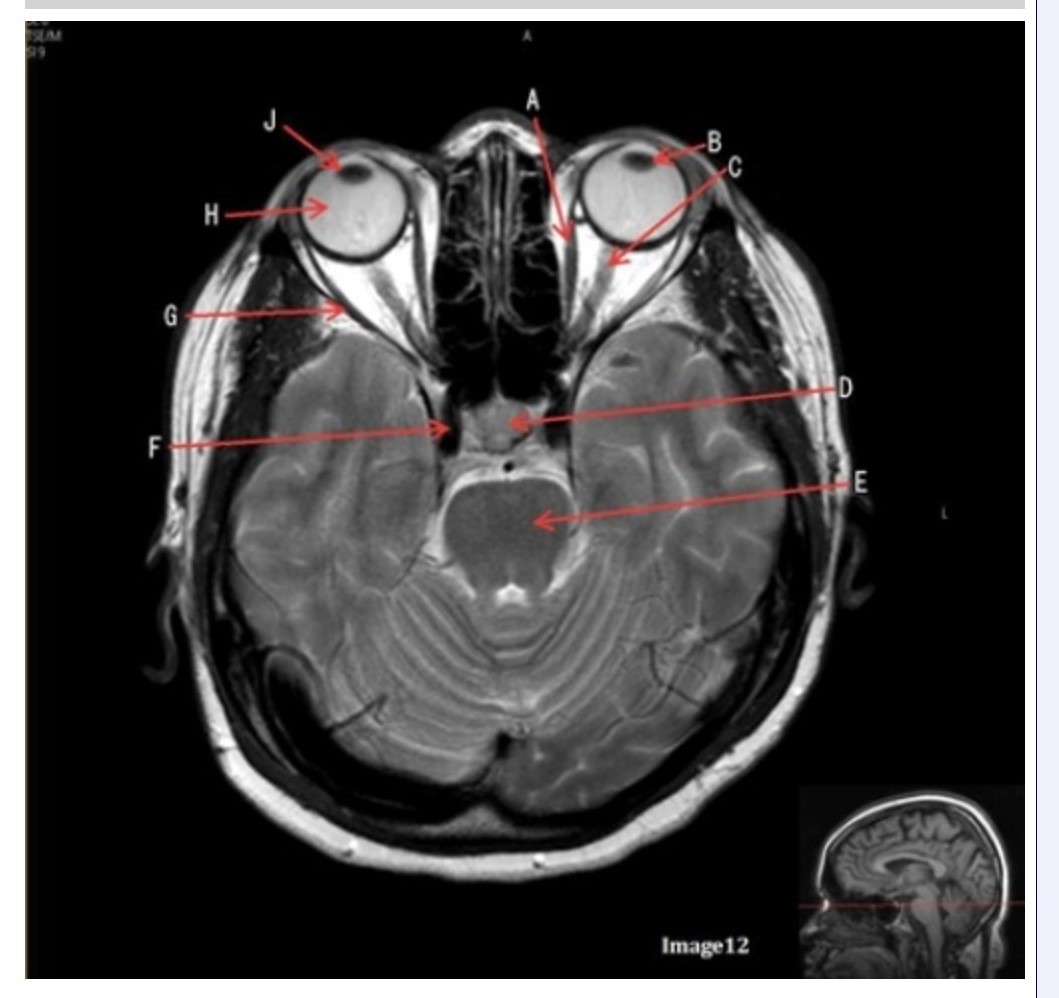

Letter H in Image 12 is pointing to:

A. Lens

B. Lateral rectus muscle

C. Medial rectus muscle

D. Internal carotid artery

E. Globe

Letter B in Image 12 is pointing to:

A. Left optic nerve

B. Lateral rectus muscle

C. Medial rectus muscle

D. Lens

E. Midbrain

Letter J in Image 12 is pointing to:

A. Globe

B. Lateral rectus muscle

C. Medial rectus muscle

D. Right lens

E. Left lens

Letter F in Image 12 is pointing to:

A. Lens

B. Lateral rectus muscle

C. Medial rectus muscle

D. Internal carotid artery

E. Globe

Letter C in Image 12 is pointing to:

A. Left optic nerve

B. Lateral rectus muscle

C. Medial rectus muscle

D. Lens

E. Midbrain

Letter D in Image 12 is pointing to:

A. Optic nerve

B. Pituitary gland

C. Globe

D. Lens

E. Midbrain

Letter G in Image 12 is pointing to:

A. Lens

B. Lateral rectus muscle

C. Medial rectus muscle

D. Internal carotid artery

E. Globe

Letter E in Image 12 is pointing to:

A. Optic nerve

B. Pituitary gland

C. Globe

D. Pons

E. Left lens